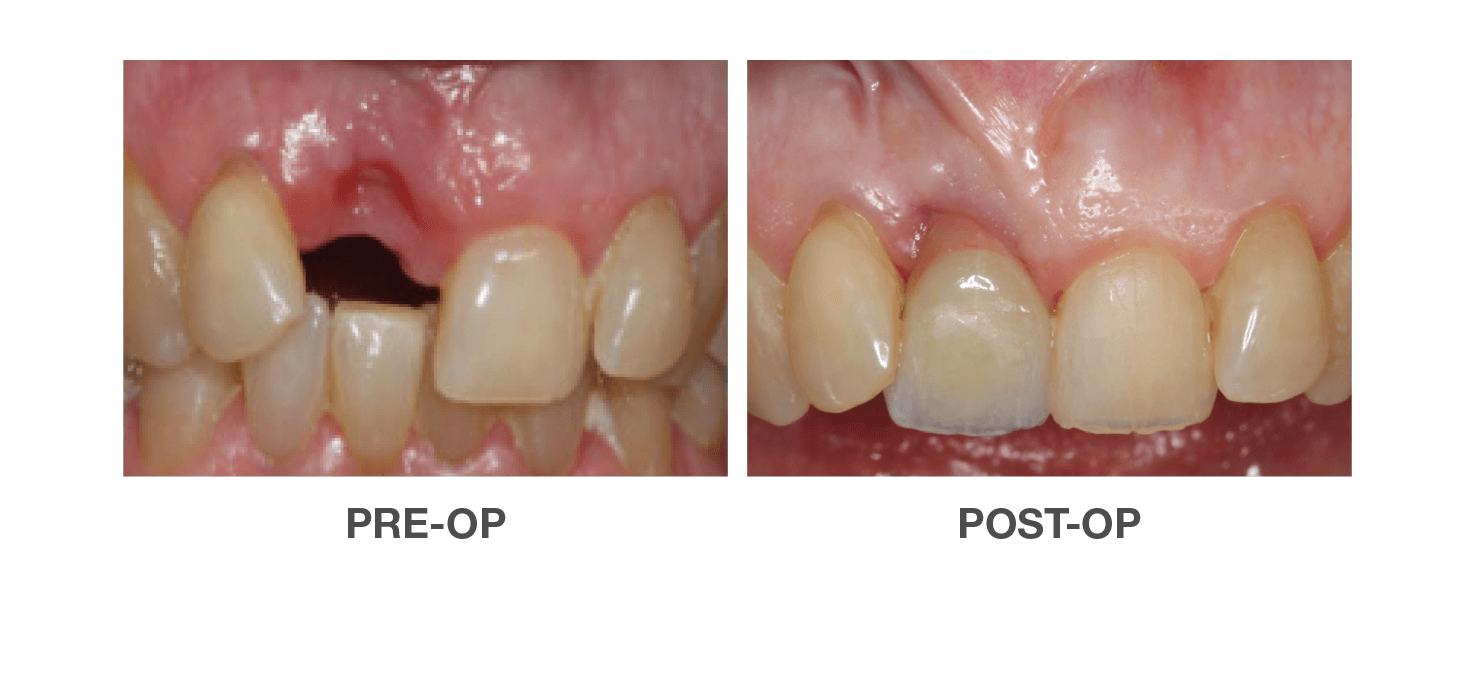

Vertical Ridge Achievement

Using OraGen® Cellular Bone Matrix

Case performed by: Dr. Edgard El Chaar, New York, NY

Horizontal Ridge Achievement

Using OraGen® Cellular Bone Matrix

Case performed by: Dr. Edgard El Chaar, New York, NY

Successful Vertical & Horizontal

Augmentation to Repair Failed Implant

Using OraGen® Cellular Bone Matrix

Case performed by: Dr. Robert Miller, Plantation FL